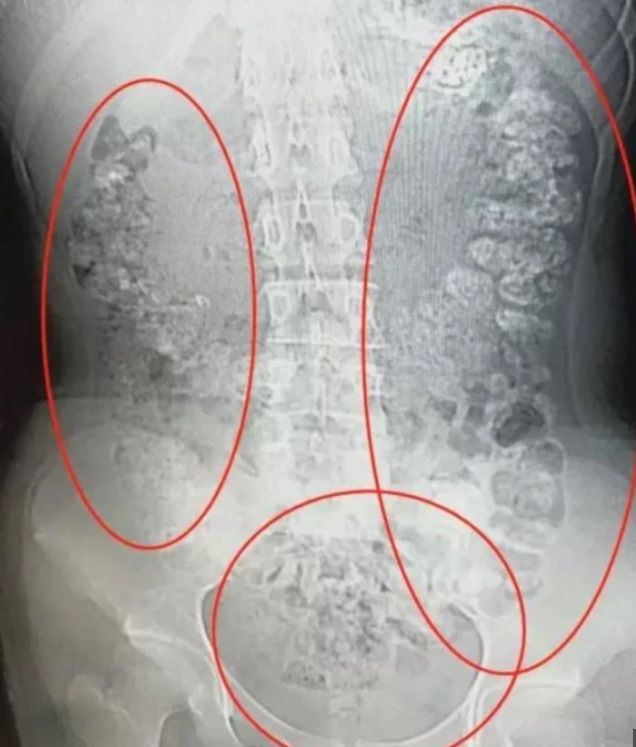

13-letni chłopak trafił na ostry dyżur w First Affiliated Hospital z Xinxiang Medical University w Chinach związku z silnym bólem brzucha. Lekarze stwierdzili u niego niedrożność jelita grubego. Prześwietlenie rentgenowskie wykazało, że blokują je dwie kulki o wymiarach dwóch i trzech centymetrów.

Kulki tapioki zalegały w okrężnicy

Kulki tapioki zalegały w okrężnicy © Facebook

Bubble tea uszkodziła okrężnicę

Bubble tea uszkodziła okrężnicę © Facebook